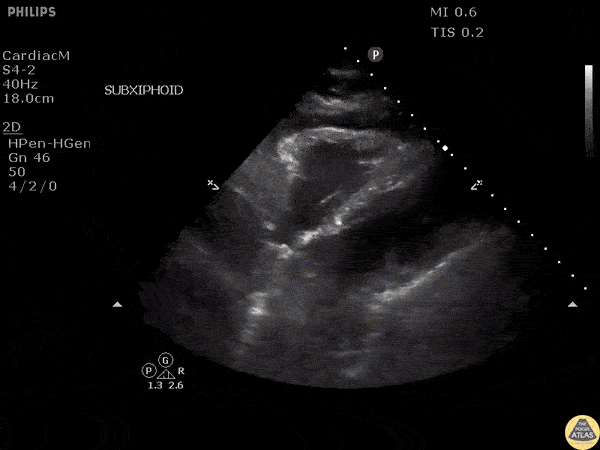

Other Cardiac Pathology - Pacer Wire Perforation

Patient with chest pain with recent history of pacemaker placement. Subxiphoid view reveals the pacer wire in the right ventricle piercing the wall, causing a pericardial effusion. Image courtesy of Robert Jones DO, FACEP @RJonesSonoEM Director, Emergency Ultrasound; MetroHealth Medical Center; Professor, Case Western Reserve Medical School, Cleveland, OH View his original post here